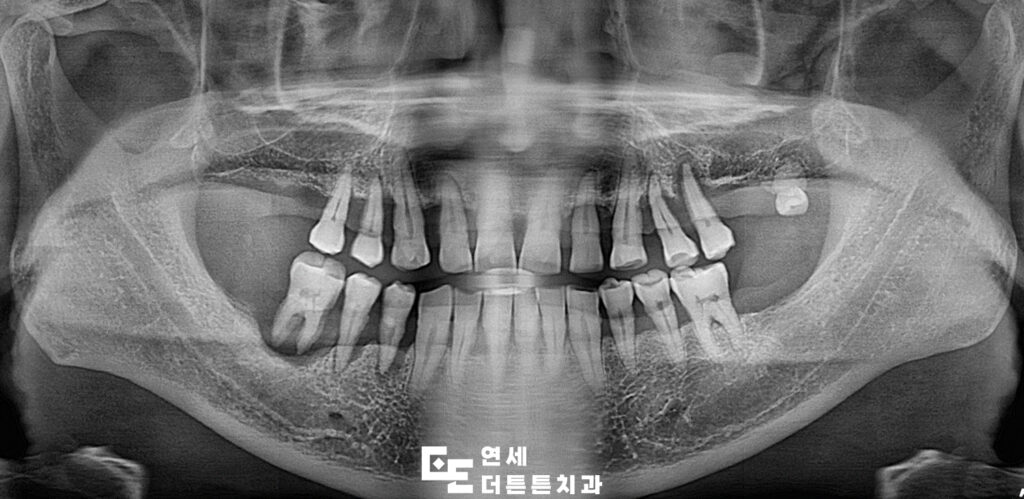

해당 환자분께서는 치아들이 전반적으로 흔들리고 상태가 좋지 않아 식사를 제대로 하기 어렵다며 본원에 내원해 주셨습니다. 기본적인 검진과 함께 파노라마 촬영을 진행한 결과, 심한 치주염으로 인해 잇몸뼈가 많이 소실되어 치아가 떠 있는 것처럼 보이는 소견이 확인되었습니다. 자연치를 유지하기에는 예후가 좋지 않다고 판단되어 발치를 진행한 뒤, 원활한 식사와 기능 회복을 목표로 어금니 부위 도봉동치과 임플란트 식립을 계획하게 되었습니다.

상태가 좋지 않았던 어금니를 발치한 뒤, 임플란트를 식립하고 최종 보철물까지 완성한 모습입니다.